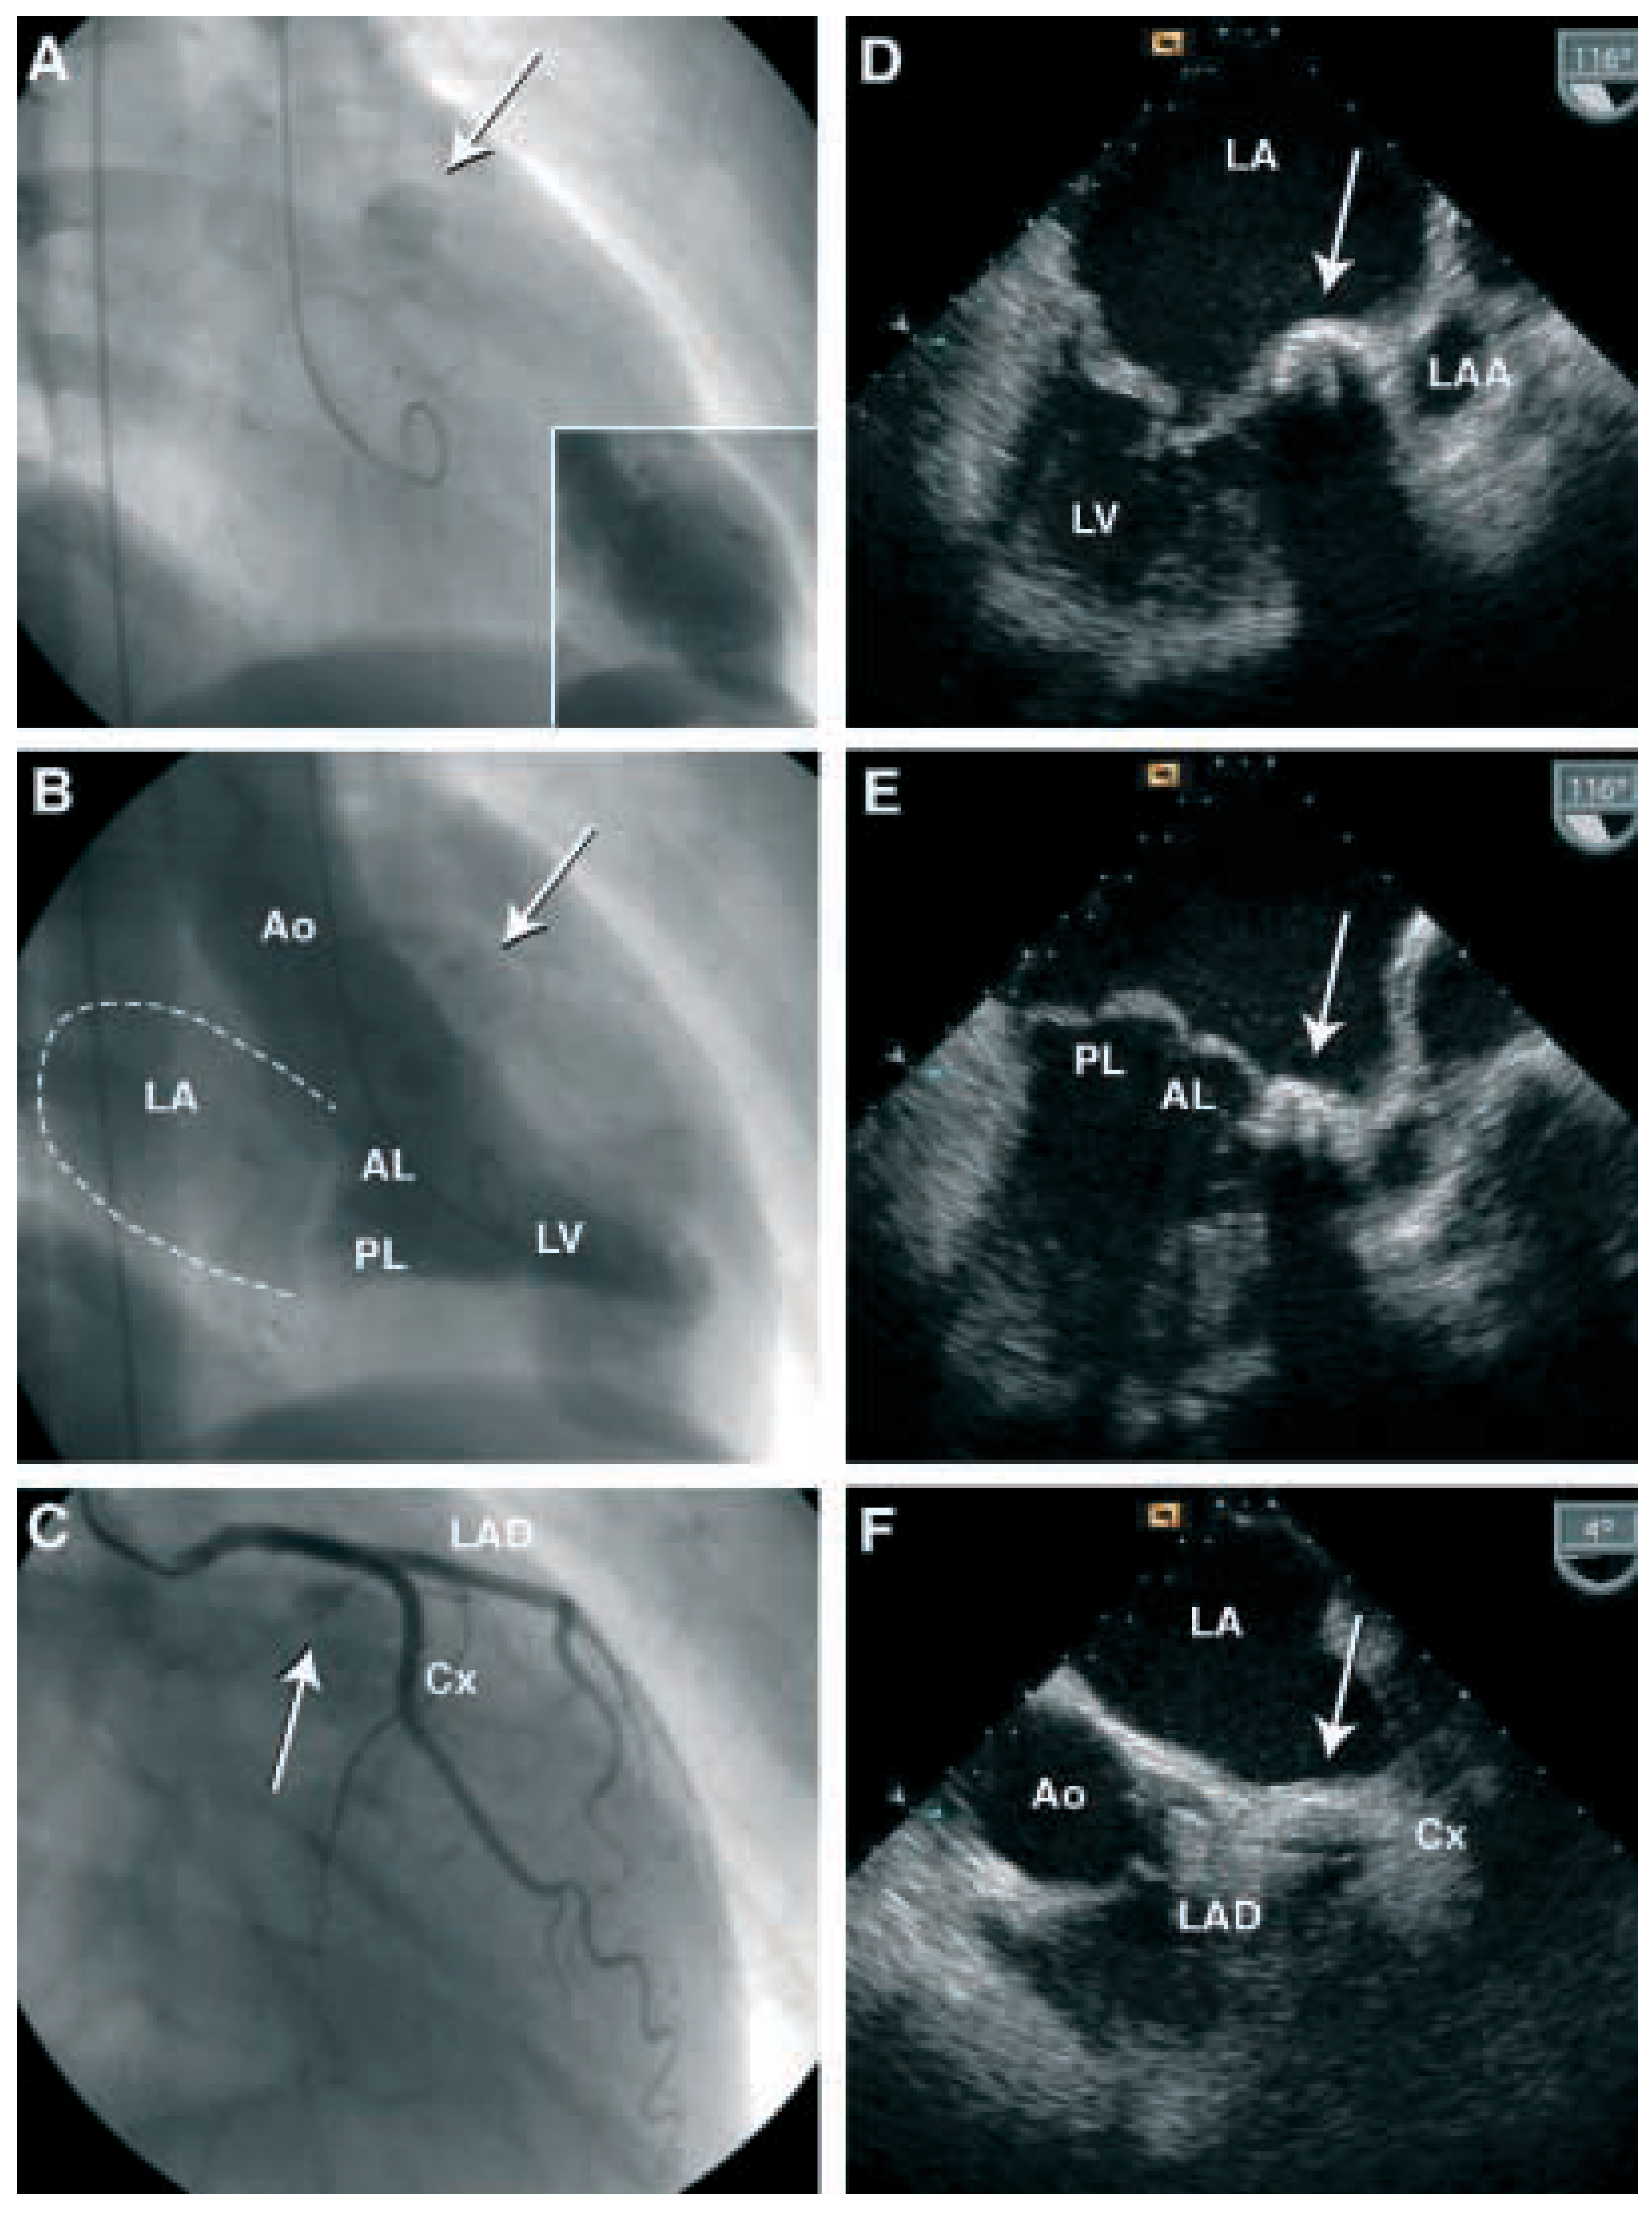

Eine Frau mit einer Intramyokardialen Verkalkung

Fallbeschreibung